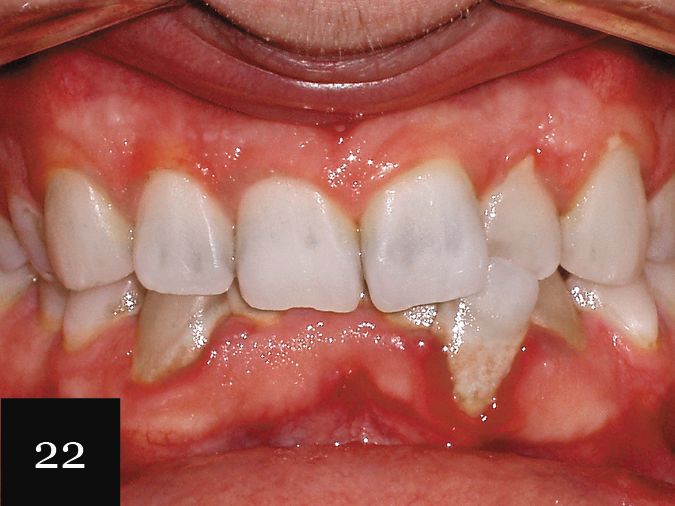

This case demonstrates the outcome of treatment on a young male patient with an anterior crossbite, deep overbite, severe crowding and periodontal disease (Figs. 21 and 22).

Again, these complex details were well captured using the Imprint 3 VPS impression material, and the patient was treated first with a series of 20 aligners, followed by a second impression and an additional 10 aligners. The hygiene issues were addressed as well, and the final result shows what we were able to achieve without resorting to periodontal surgery or grafting (Figs. 23 and 24).